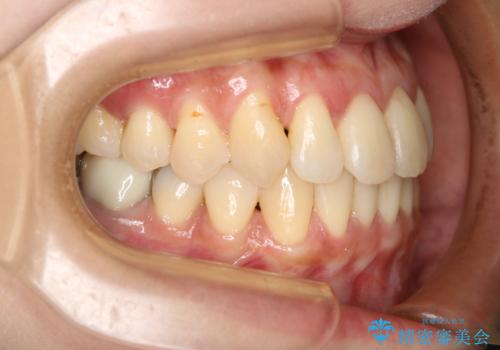

前歯が内側に入っている:インビザライン治療

- 上の前歯は内側に入っていることが気になりご相談にいらした方です。インビザラインにて治療を行いました。

1週間でのマウスピース交換を指示していましたが、20時間以上使えない時があると不安との事で、2週間ごとの交換にしていました(実際はほとんど20時間以上使用できていたようです)。治療終了まで時間はかかりましたが、最終的に綺麗に並べることができ、大変喜んでいただけました。